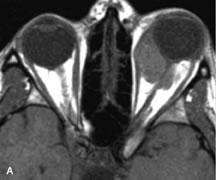

Tl relaxation time is the time required for the energized nuclei to give up the excess energy that was acquired from the RF pulse (high-energy state) and re-establish equilibrium (low-energy state) with the main magnetic field. The excess energy is released by these excited nuclei to the surrounding molecular environment, or lattice, and results in T1 relaxation, also called spin-lattice relaxation time. In different biologic tissues, hydrogen has a Tl ranging from a few hundred milliseconds to a couple of seconds. This range exists because local tissue factors affect the ability of specific protons to give up energy to the surrounding tissues. For example, hydrogen atoms attached to the carbon atoms of fat molecules relax much more rapidly than those attached to the oxygen atoms of water molecules. Viscosity, concentration, temperature, and molecular environment of the hydrogen atoms in the tissues also affect the T1 relaxation time. On a T1-weighted orbital image, fat, which has a very short T1 relaxation time, yields a high-intensity signal; the rectus muscles, which have an intermediate T1, yield an intermediate-intensity signal; and the vitreous, which has a long T1, yields a low-intensity signal (Fig. 8).5,8,16